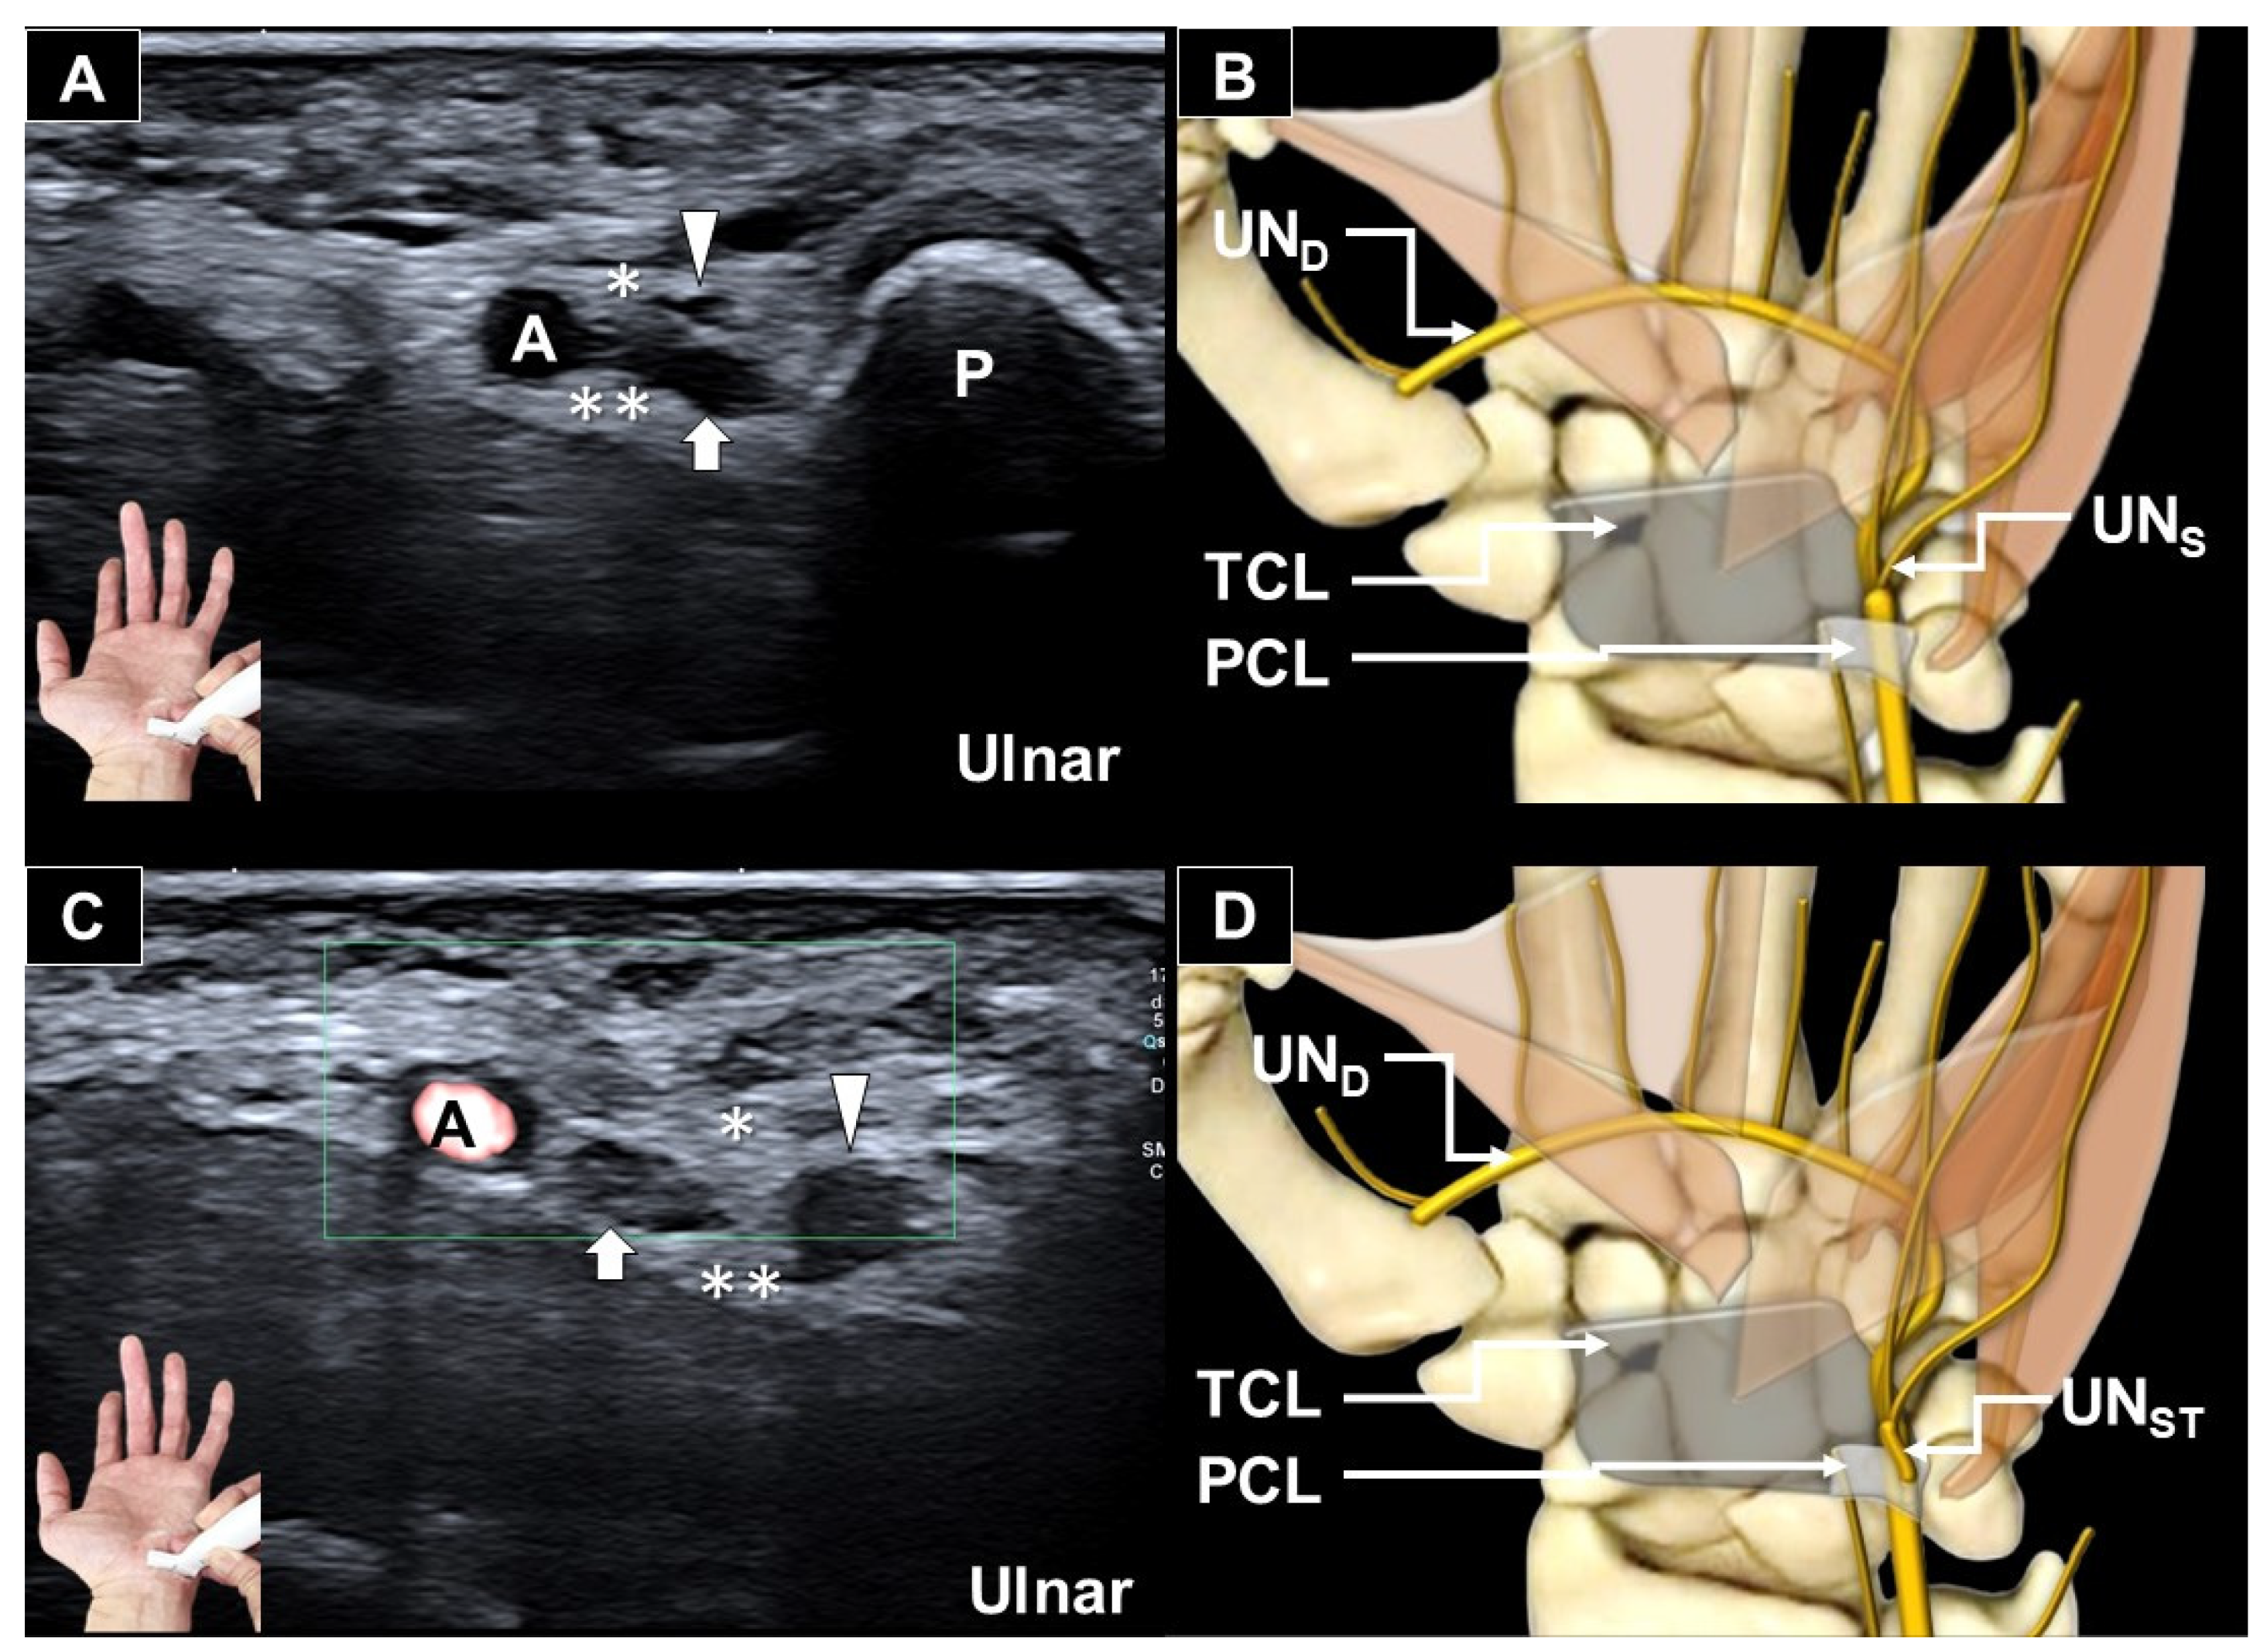

Ultrasonograhic Identification of the Entrapment of a Transligamentous Sensory Branch of the Ulnar Nerve

- Vargas, C.R.; Chepla, K.J. Report of a Transligamentous Ulnar Nerve Sensory Branch. Hand 2020, 15, NP11–NP13. [Google Scholar] [CrossRef] [PubMed]